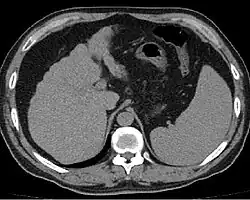

Диагностика

Характерно повышение активности АЛТ, АСТ, щелочной фосфатазы, лейкоцитоз. При гепатолиенальном синдроме может развиваться гиперспленизм, проявляющийся лейкопенией, тромбоцитопенией, анемией и увеличением клеточных элементов в костном мозге.

Расширенные и извитые венозные коллатерали выявляются при ангиографии, компьютерной томографии, ультразвуковом исследовании или в ходе оперативного вмешательства.